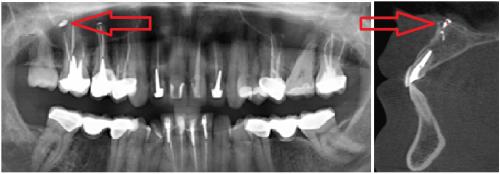

![]() | ![]() | ![]() |

| Выход пломбировочного материала за верхушку зуба вызывал жестокие боли во второй ветви тройничного нерва у мужчины. Вид сбоку:

зуба, кружком обведен | Стреляющая боль во всех трех ветвях была следствием плохого кровообращения в мозговых отделах тройничного нерва у пожилой женщины. Кружком обведен участок мозга, пострадавший от закупорки одного из сосудов головного мозга. Проверить сосуды головы и шеи | Невралгия тройничного нерва была у молодой женщины из-за давления одной из мозговых артерий на корешок тройничного нерва. На МР-томограмме видно пересечение тройничного нерва (идет вертикально) с артерией (идет горизонтально). Артерия оказывала давление на тройничный нерв в месте его выхода из ствола мозга. |

Стрелками показаны фрагменты пломбировочного материала (вид спереди и сбоку), который при пломбировании канала выпал за пределы зуба и «упёрся» в область залегания ветви тройничного нерва. У пациента долго болел зуб после лечения пульпита, затем онемела верхняя губа и часть щеки.

Стрелками показаны кисты корней зубов (вид спереди). Кисты в данном случае представляют собой замкнутые очаги инфекционного воспаления. Киста со временем набухает и создает давление на ветви тройничного нерва, отсюда онемение лица и боль. Осложнение после лечения пульпита.

2. Рентгеновские исследования. На обычных рентгенограммах и панорамных снимках не всегда видна истинная картина болезни. Мы рекомендуем конусно-лучевую компьютерную томографию с функцией защиты от дефектов изображения от пломбировочного материала и протезов.